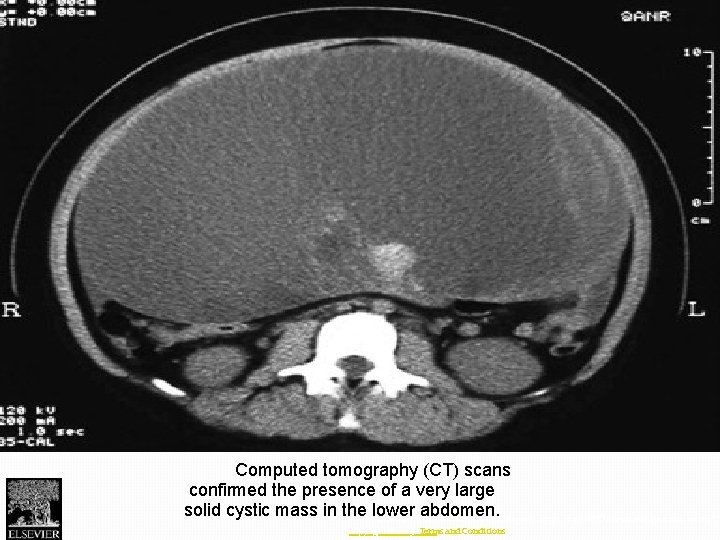

Fig. 1 Computed tomography (CT) scans confirmed the presence of a very large solid

Fig. 1 Computed tomography (CT) scans confirmed the presence of a very large solid cystic mass in the lower abdomen. Journal of Pediatric Surgery Case Reports 2013 1, 174 -176 DOI: (10. 1016/j. epsc. 2013. 05. 010) Copyright © 2013 Terms and Conditions